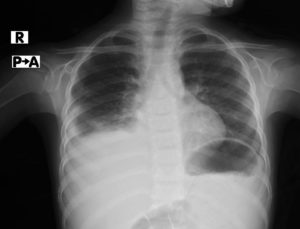

الطبيب المختص بمشفى الأمل أجرى فحص دقيق للطفل حيث تبين بعد الاصغاء للصدر وجود خرخرة ناعمة بالساحة الرئوية اليمنى، طلب “الطبيب” إجراء تحاليل وصورة أشعة، تبين بعدها وجود كثافة بالساحة الرئوية اليمنى وبنتيجة التحاليل الدم تبين ارتفاع عالي بنسبة الـ CRP حيث كانت قيمتها عند القبول 218.

وضع الطفل تحت العناية بجناح الأطفال وبعد 3 أيام تم إجراء ايكو للصدر، أظهرت الصورة وجود انصباب جنب أيمن، نتيجة إصابته بأنفلونزا الخنازير H1N1 حيث قمنا بتغيير التغطية وإعطاء صادات حيوية مناسبة للطفل مع فترة علاج استمرت ثلاثة عشر يوم تحت العناية المركزة، تم تخريجه بحالة عامة ممتازة وصحة جيدة بعدها، بحسب نتيجة التحاليل وصورة أشعة. بحسب نتيجة التحاليل وصورة أشعة.